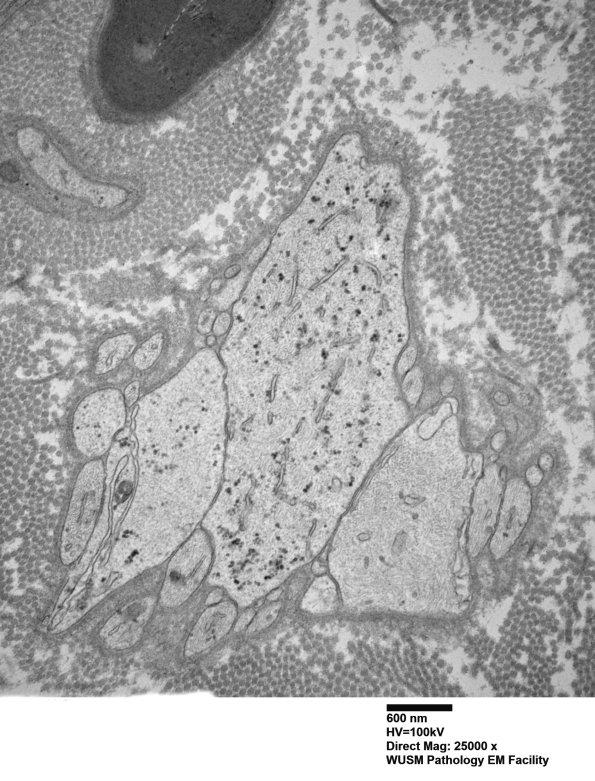

These are Schwann processes forming bands of Büngner. In some cases Schwann cells are enlarged and occasionally dilated with pale cytoplasm, mimicking demyelinated axons in plastic sections. (electron micrograph)